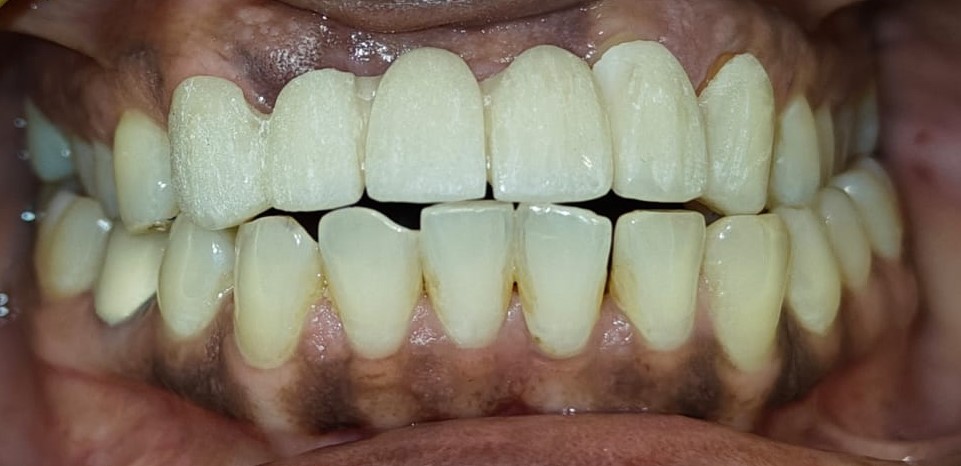

Before Before